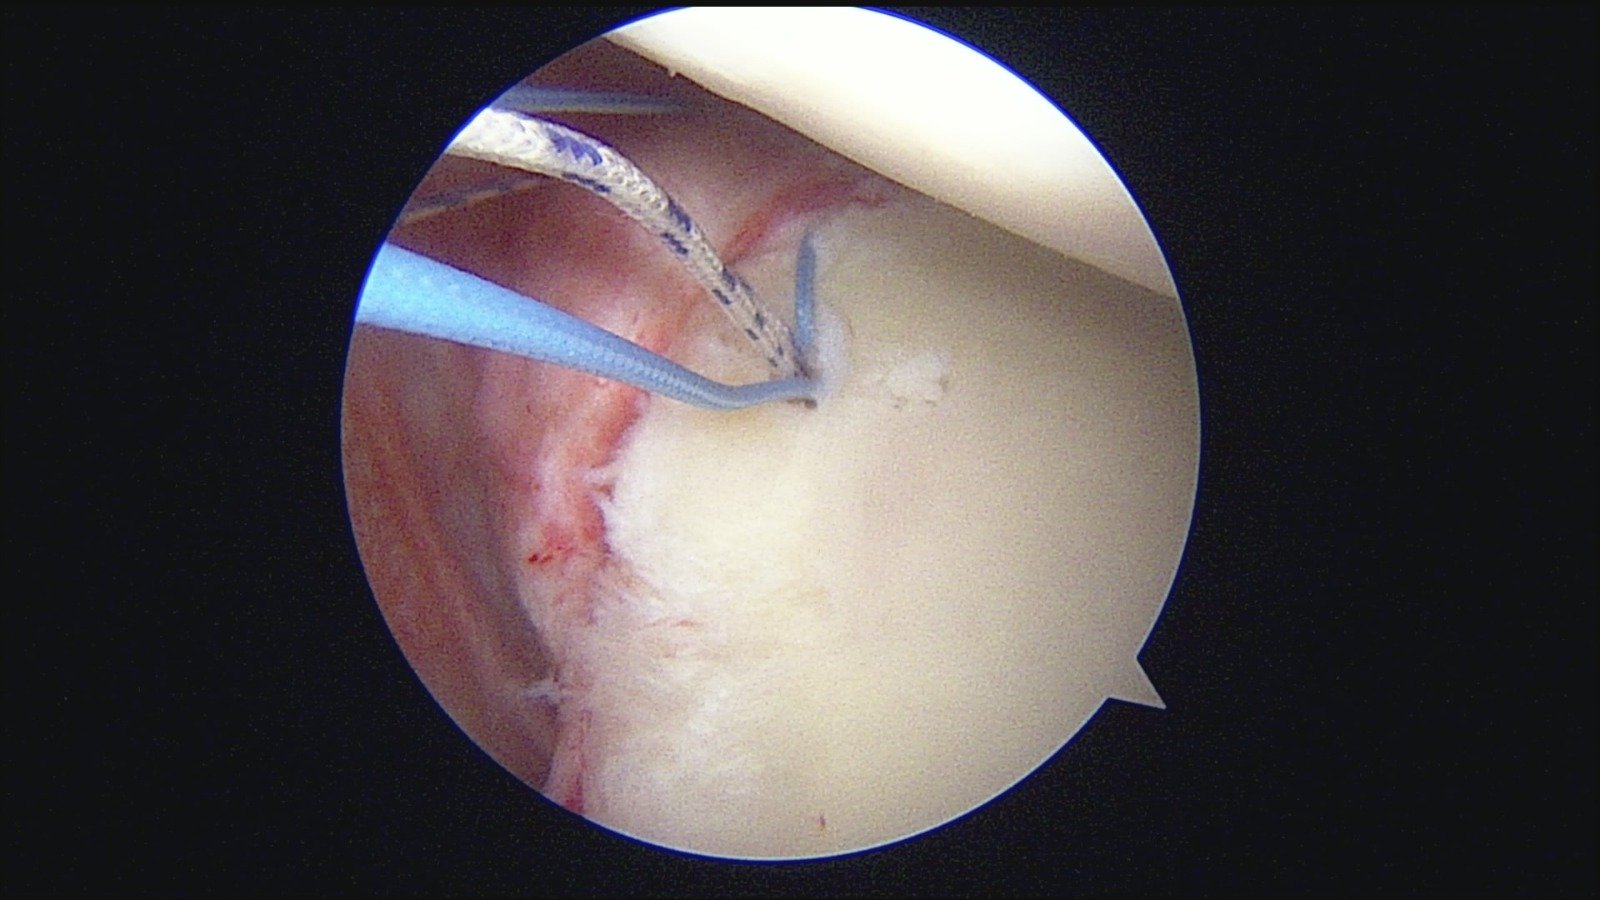

GalleryShoulder rotator cuff repair Meniscus root repair Meniscus repair Bankart repair for recurrent shoulder dislocation ACL reconstruction Machines Instruments